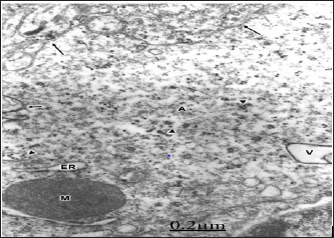

The swollen and clear astrocytes display marked degenerative changes induced by brain edema in comparison with those exhibited by neuronal cells. Areas of focal necrosis and fragmented limiting plasma membrane, over-distended rough endoplasmic reticulum cisterns with extended degranulated areas, and vacuoles of smooth endoplasmic reticulum with necrotic limiting membrane are found [80-82] (Figure 8). Oligodendroglial cells show also marked edematous changes featured by lacunar enlargement of rough endoplasmic reticulum and nuclear envelope, detachment of membrane bound ribosomes, swollen mitochondria associated to rough endoplasmic reticulum, and discontinuous plasma membrane [83,84]. (Figure 9). The endoplasmic reticulum is a subcellular compartment playing a fundamental role in the folding and processing of newly synthesized membranes and secretory processes, reactions which are strictly calcium/dependent. Severe disruption of neuronal Ca2+ homeostasis leading to a lethal Ca2+ overload as occurs in brain ischemia, can initiate a cascade of destructive processes which lead to the death of neurons during cerebral ischemia [85-86]. As stated above endoplasmic reticulum function is disturbed in many acute and chronic diseases of the brain, such as Parkinson's and Alzheimer's diseases [87]. Therefore, endoplasmic reticulum dysfunction is basically important to elucidate the pathogenetic mechanisms of neurodegeneration.

Figure 8: Brain trauma. Swollen and clear astrocyte cell (A) depicting fragmented plasma membrane (long ar-rows) and areas of focal necrosis (short arrow), degran-ulated and dilated rough endoplasmic reticulum cisterns (ER), glycogen granules (arrowheads), and a vacuole (V) limited by necrotic membrane. Note the degenerated and dense mitochondrion (M) associated with rough endo-plasmic reticulum X. 60.000.